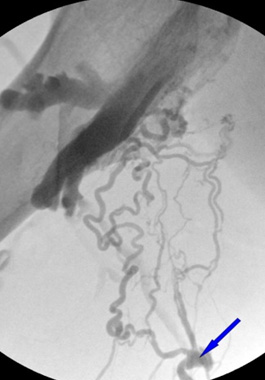

For numbness and coldness, a thorough examination is the most important step. These symptoms in the hands and feet can have many different causes, making them difficult to treat without identifying the exact source. Accurate diagnosis through detailed examination is essential for proper treatment. At Sun Vascular Clinic, we perform advanced diagnostic evaluations to determine the precise cause of numbness and coldness. Your doctor, with extensive expertise in vascular care, uses state-of-the-art ultrasound equipment comparable to that of university hospitals to carefully examine the deep veins, superficial veins, perforating veins, and connecting junctions, as well as the microcirculation. If the examination reveals that the numbness or coldness is due to vascular abnormalities, treatment is performed to strengthen the weakened vein walls and restore normal blood flow by correcting venous reflux.

In cases of saphenous vein reflux, the junction between the saphenous vein and the deep vein is sealed horizontally and closely to form an angle near zero degrees, preventing recurrence.